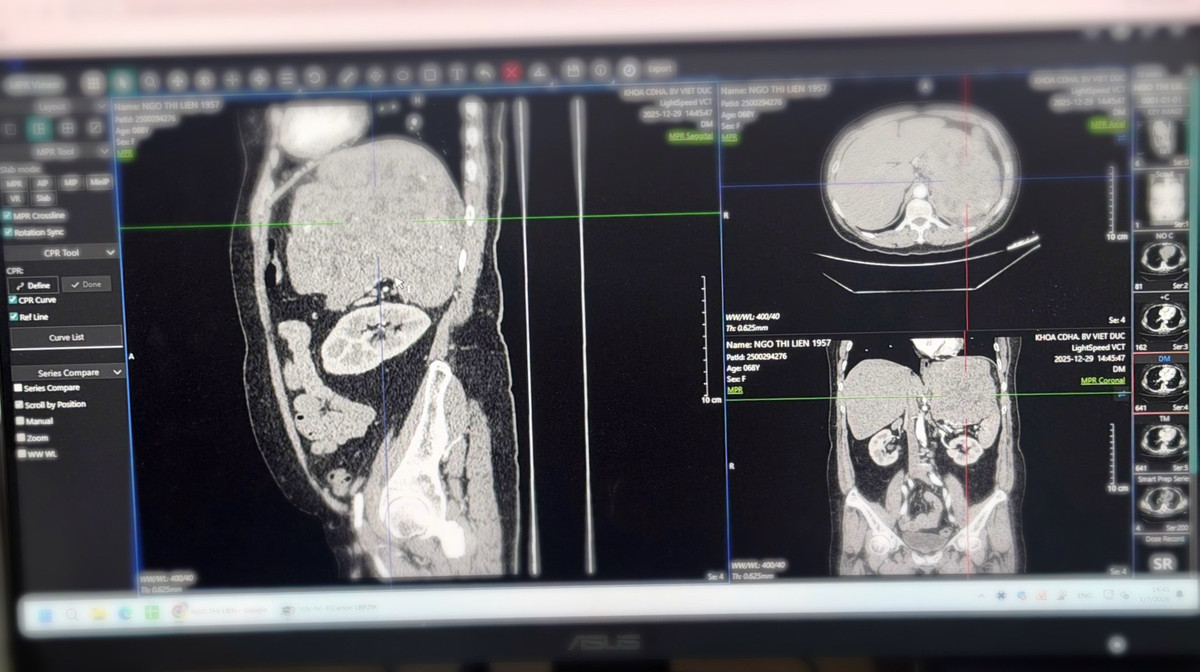

Người bệnh nữ 69 tuổi (Hải Phòng) được chẩn đoán u sau phúc mạc kích thước khoảng 20cm. Trước đó, người bệnh đi khám tại Bệnh viện Đa khoa Hải Phòng và sau đó quyết định chuyển lên Bệnh viện Hữu nghị Việt Đức để được điều trị chuyên sâu.

Hình ảnh phim chụp khối u kích thước 20cm của bệnh nhân - Ảnh BVCC

Sau khi thăm khám, hội chẩn và đánh giá kỹ lưỡng bằng các phương tiện chẩn đoán hình ảnh hiện đại, các bác sĩ đã chỉ định phẫu thuật cắt bỏ khối u sau phúc mạc.